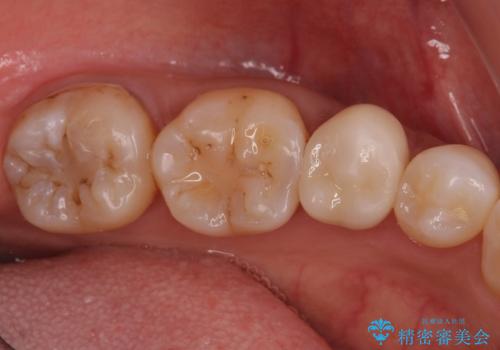

- 出産して落ち着いたから虫歯のチェックをしてほしいとのことで来院されました。

左下の奥歯に詰まっている樹脂の周辺が虫歯になっていたため、治療を進めていくこととなしました。